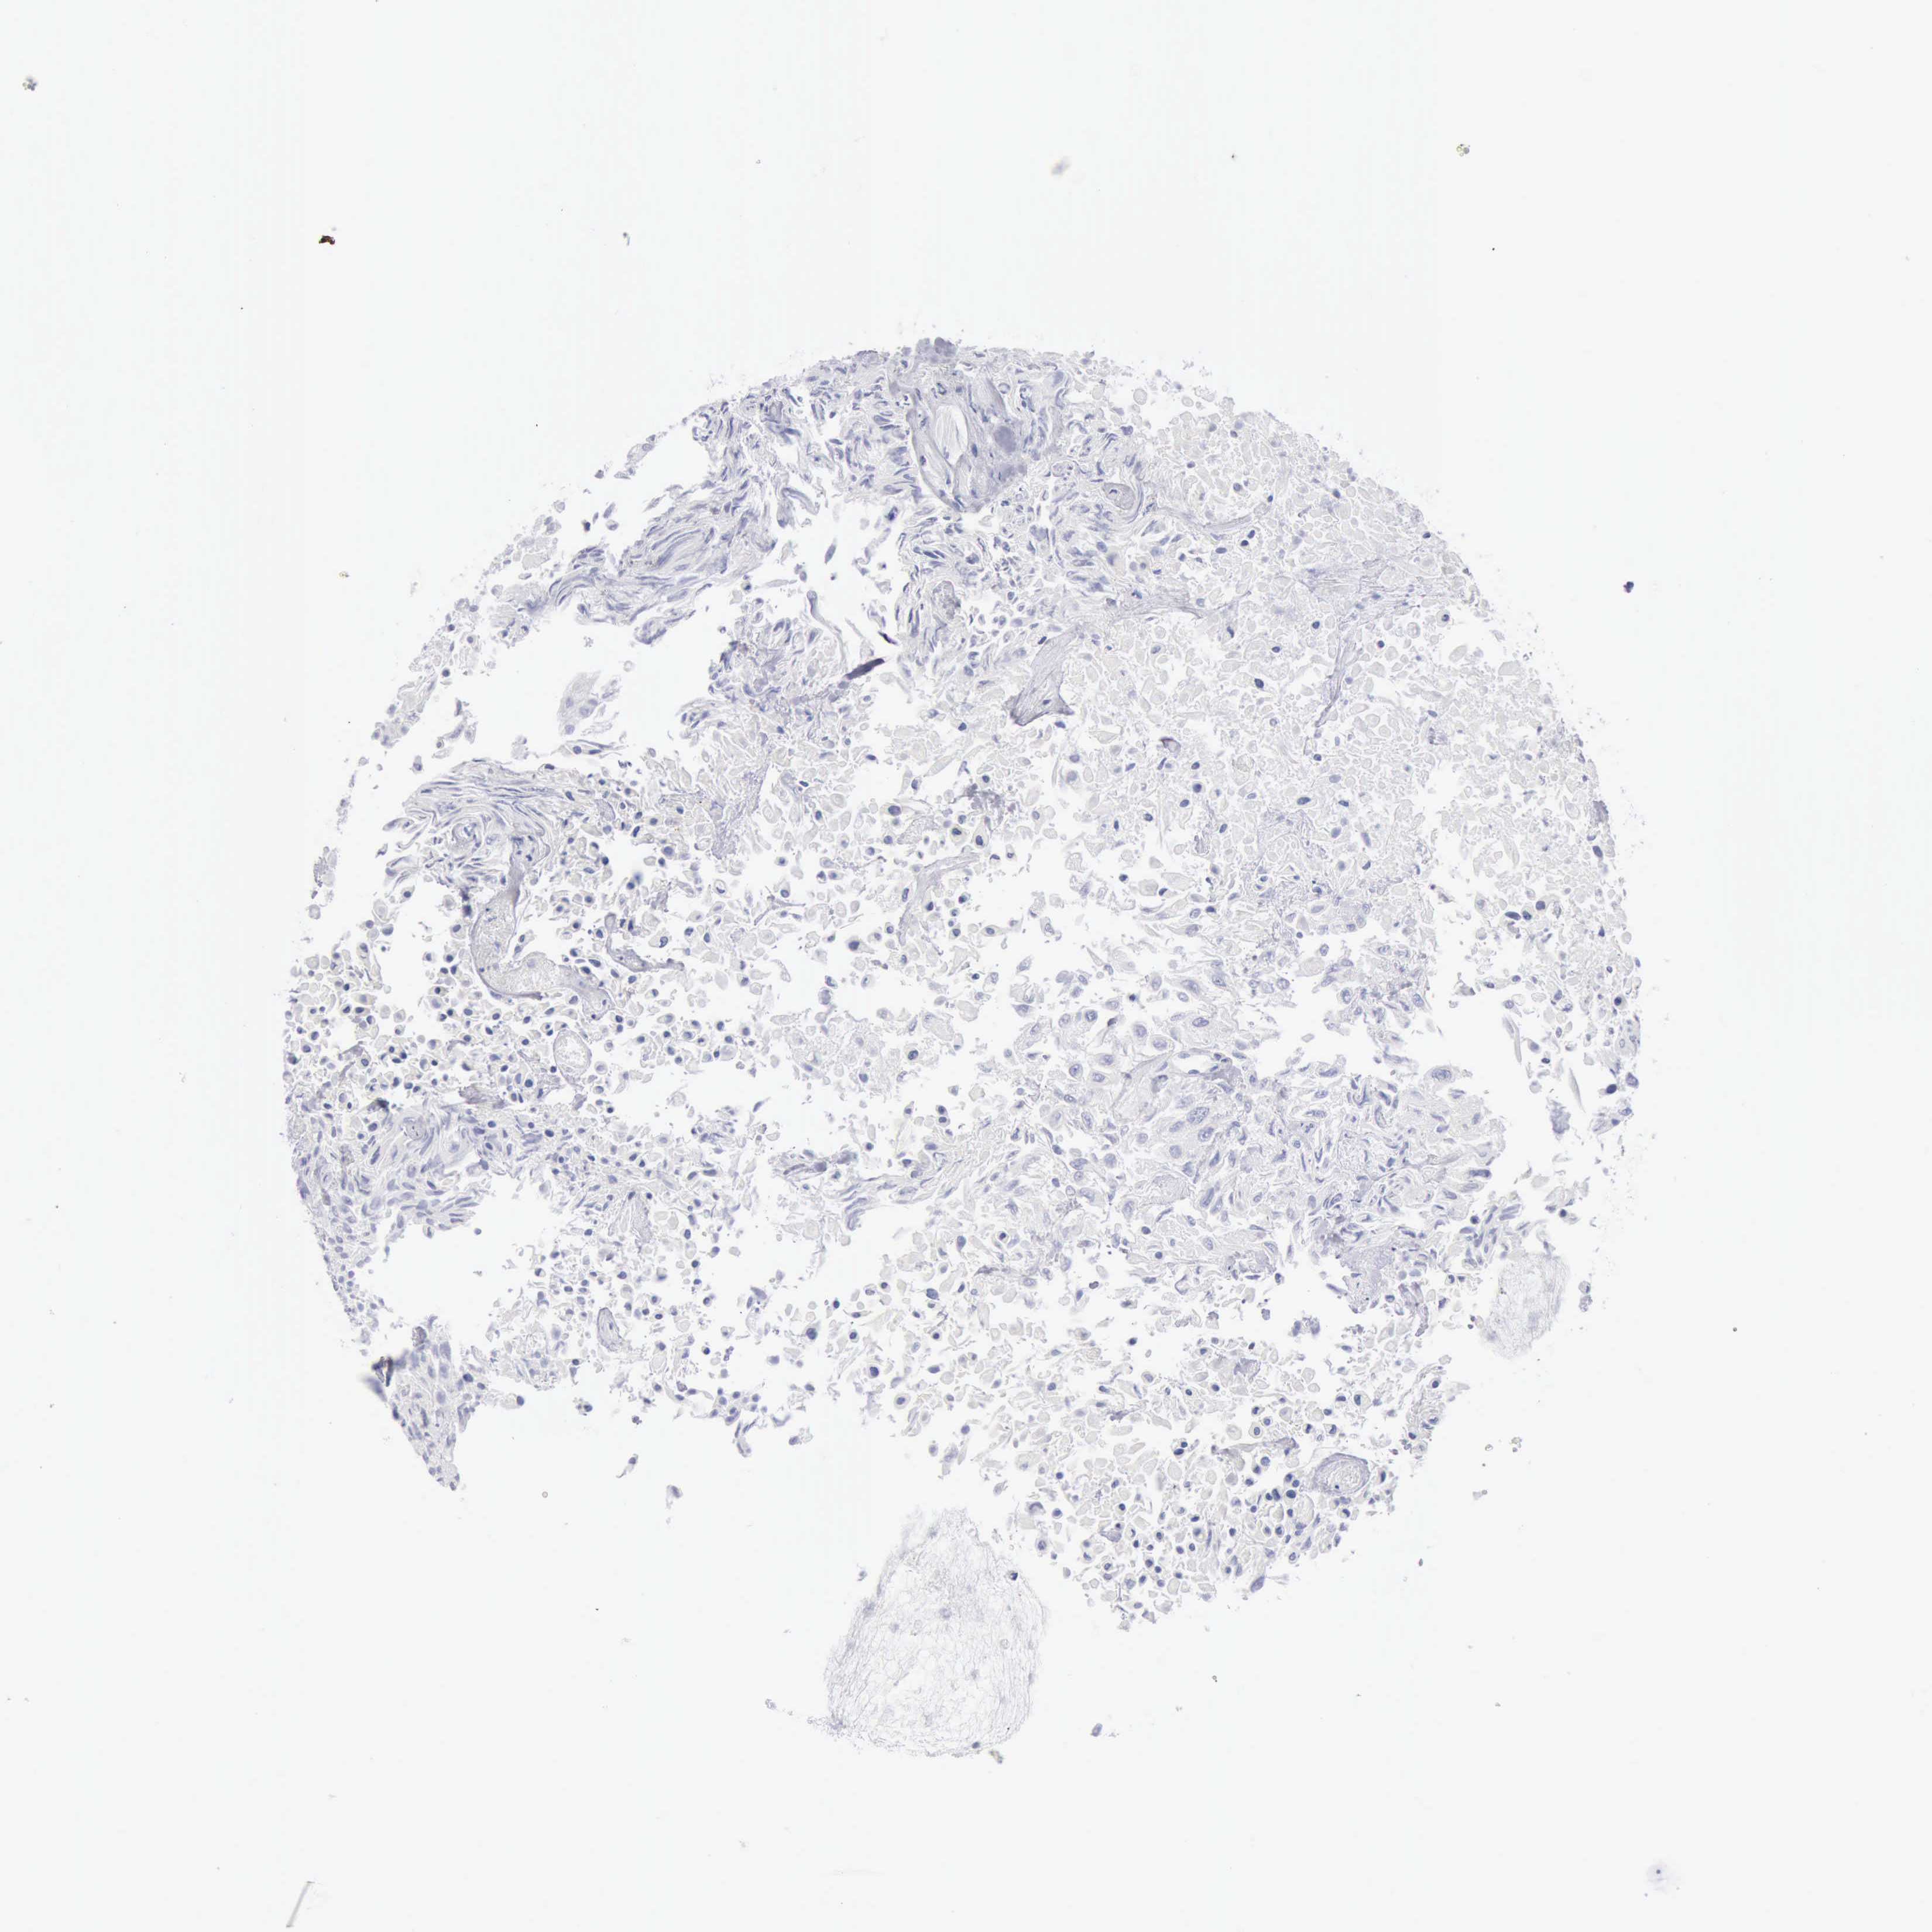

UROTHELIAL CANCER - Protein expressioni

A mouse-over function shows sample information and annotation data. Click on an image to view it in a full screen mode. Samples can be filtered based on level of antibody staining by selecting one or several of the following categories: high, medium, low and not detected. The assay and annotation is described here.

Antibody stainingi

Antibody staining in the annotated cell types in the current human tissue is reported as not detected, low, medium, or high, based on conventional immunohistochemistry profiling in selected tissues. This score is based on the combination of the staining intensity and fraction of stained cells.

Each image is clickable and will lead to virtual microscopy that enables deeper exploration of all samples and also displays staining intensity scores, fraction scores and subcellular localization as well as patient and tissue information for each sample.

Antibody HPA003418

Antibody CAB000376

Urothelial carcinoma, High grade

Urothelial carcinoma, Low grade